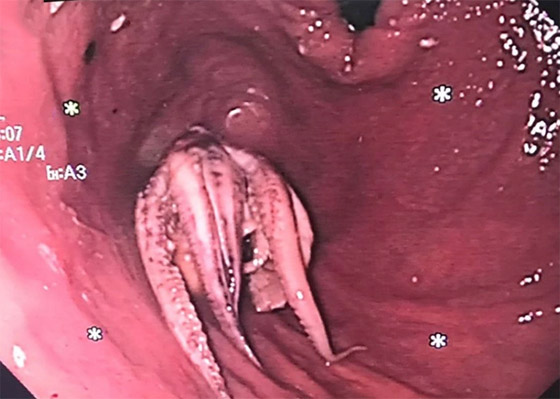

صُدم الأطباء بسنغافورة لاكتشاف أخطبوط استقر في مريء رجل أثناء إجراء فحص الجهاز الهضمي لمعرفة سبب القيء لديه. وأدرك الرجل السنغافوري أن هناك خطأ ما عندما بدأ بالتقيؤ بعد تناول وجبة تضمنت أخطبوطا نيئا. وعندما أدرك أنه يعاني أيضا من مشكلة في البلع، أصيب الرجل بالذعر وقرر بسرعة زيارة قسم الطوارئ في مستشفى تان توك سينغ.

أجرى الأطباء هناك فحصا سريعا بالأشعة المقطعية، والذي كشف عن وجود كتلة فائقة الكثافة في مريء الرجل، لكنهم لم يتمكنوا من التأكد مما كانت عليه دون تنظير المريء، والذي يتضمن إدخال أنبوب صغير ومرن بكاميرا في نهايته، واكتشفوا بها أن الرجل لديه أخطبوط كامل عالق في حلقه.

الأطباء ينقذون رجلا علق أخطبوط في حلقه! صورة رقم 1

وشارك معهد الجمعية الأميركية للجهاز الهضمي (AGA) صورا مأخوذة من كاميرا المنظار الداخلي، وتُظهر المخلوق ذي المجسات الثمانية العالق في مريء الرجل. في البداية، جرب الأطباء "تقنية الدفع" ولكن سرعان ما اتضح أن الأخطبوط لن ينزل للأسفل، والضغط المفرط قد يؤدي إلى تمزق المريء. لذلك كان عليهم استخدام الملقط للإمساك بالمخلوق البحري وسحبه خارج المريء. وليس من الواضح لماذا ابتلع الرجل الأخطبوط كله، ولكن لحسن الحظ تعافى جيدا وخرج من المستشفى بعد يومين.